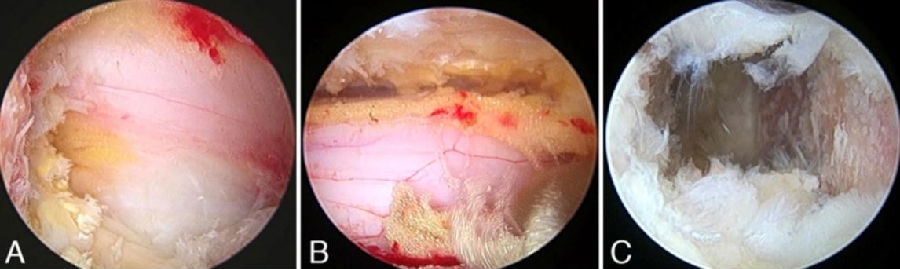

二、硬膜破裂(2.27%)

是常见并发症之一,发生率约2.9%。临床常见表现为头痛,包括直立性头痛、间歇性头痛、用力时头痛、眩晕、颈后疼痛、颈部僵硬、恶心、复视、畏光、耳鸣、视力模糊、脑脊液漏形成、假性脑膜膨出、脑膜炎、蛛网膜炎和硬膜外脓肿等。

常见原因:

学习曲线早期,经验不足

操作时出血较多易造成视野不清晰

硬脊膜与黄韧带粘连

过度追求完美增加不必要的手术操作

治疗:

硬膜破裂直径<4 mm:保守治疗

硬膜破裂直径 4-12mm:纤维蛋白补片

硬膜破裂直径>12mm:

边缘规则:内镜下修补(钛夹)

边缘不规则: 显微镜下硬膜修补

思考和建议:

术中精细操作,避免硬膜囊损伤

钙化的椎间盘及翻修手术谨慎应用UBE

损伤较小:紧密缝合

损伤较大:显微镜或通道下硬膜修补